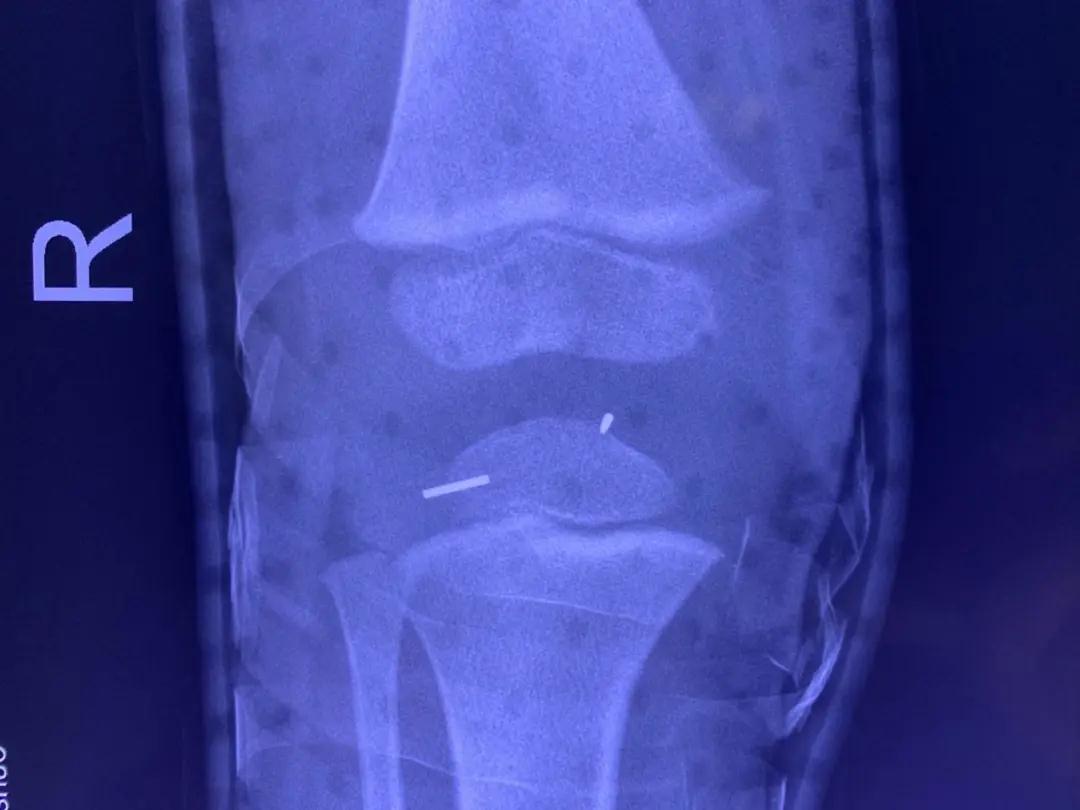

残留在孩子体内的缝衣针

入院后经过检查,发现孩子断在右膝盖中的钢针共有两截,每截大概有1.5厘米,且随着关节运动,钢针位置已经发生偏移。这给手术取出造成了不小困难。该院骨科副主任医师孙克明为晗晗进行急诊手术,在孩子的膝关节囊内,关节腔外角分别将两截断针精准定位并取出。